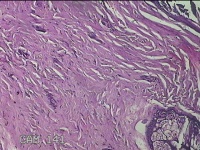

右颈部皮肤肿物

性别

女

年龄

29岁

临床诊断

纤维瘤

一般病史

右颈部皮肤起肿物10年左右。

标本名称

大体所见

灰白暗红色肿物0.3x0.2x0.1cm一个,表面光滑。

图1